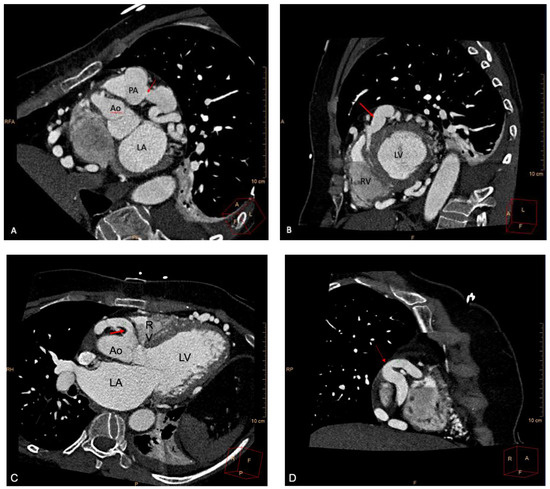

2. Case Report

Case Presentation